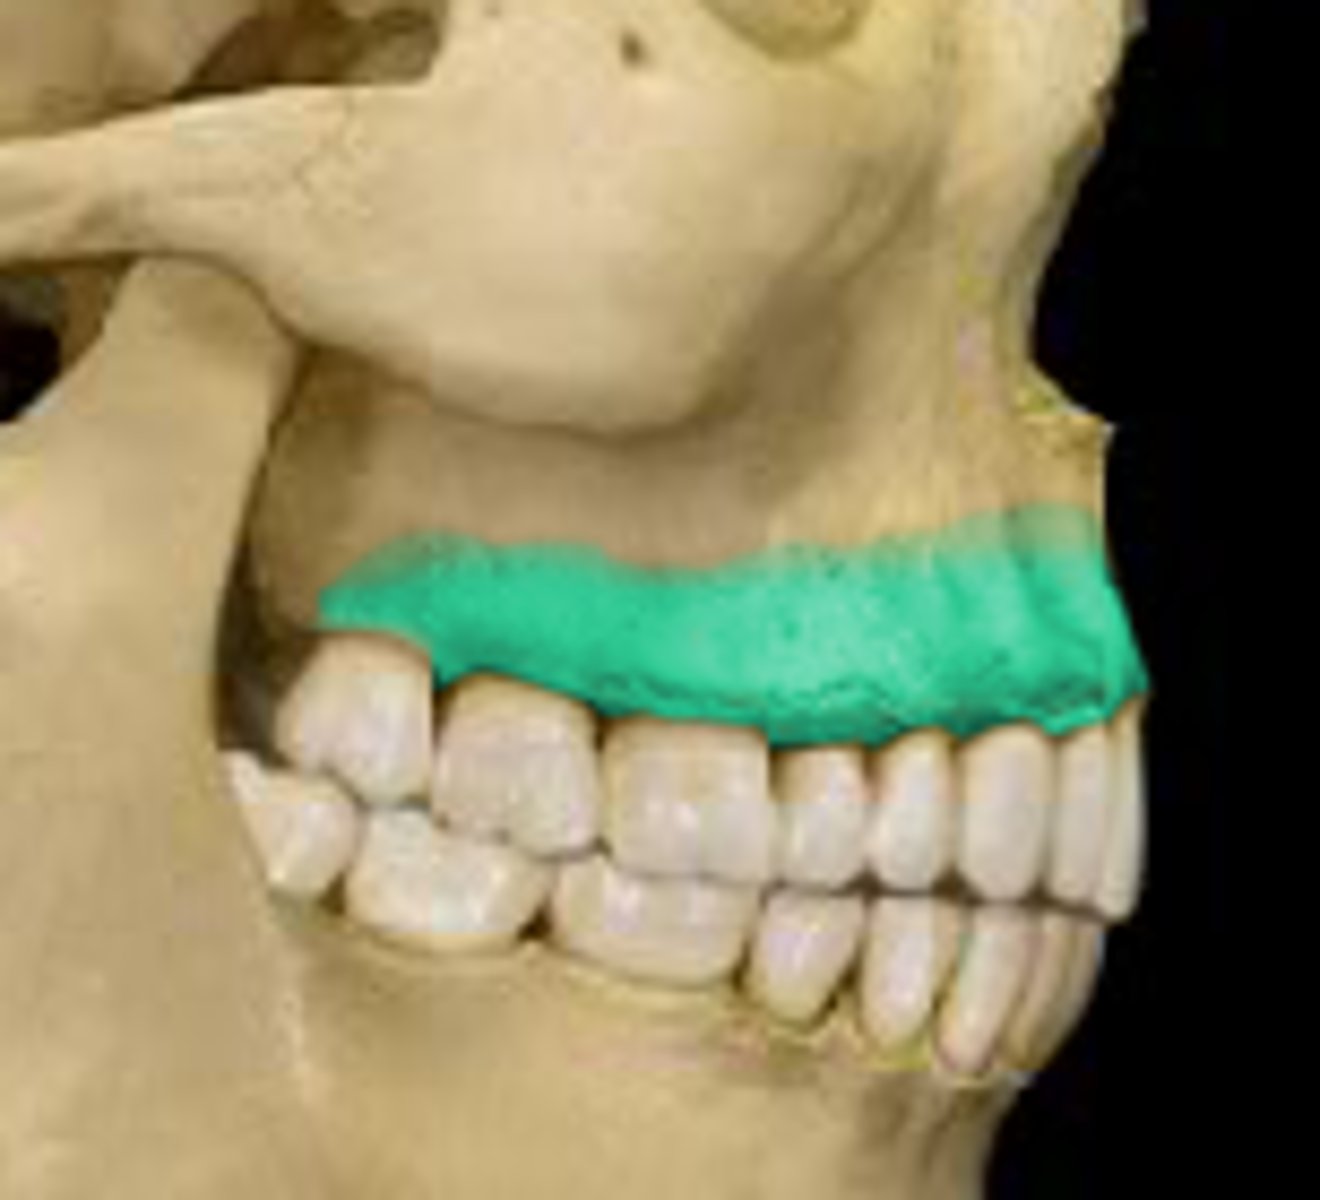

Maxillary tuberosity

- small, bony prominence behind the last upper molar

What is this and where is it located?

The horizontal section known as the body and two vertical sections known as the rami.

What are the two main sections of the mandible?

At the gonion, also known as the angle of the mandible.

Where do the body and rami of the mandible meet?

Symphysis

- faint ridge running vertically in the midline

What is this , and where is it found ?

1st year of life

When do the 2 halves of the body fuse ?

Mental protuberance

- prominence at the lower border of the symphysis (mental point/ chin)

What is this and where is it found?